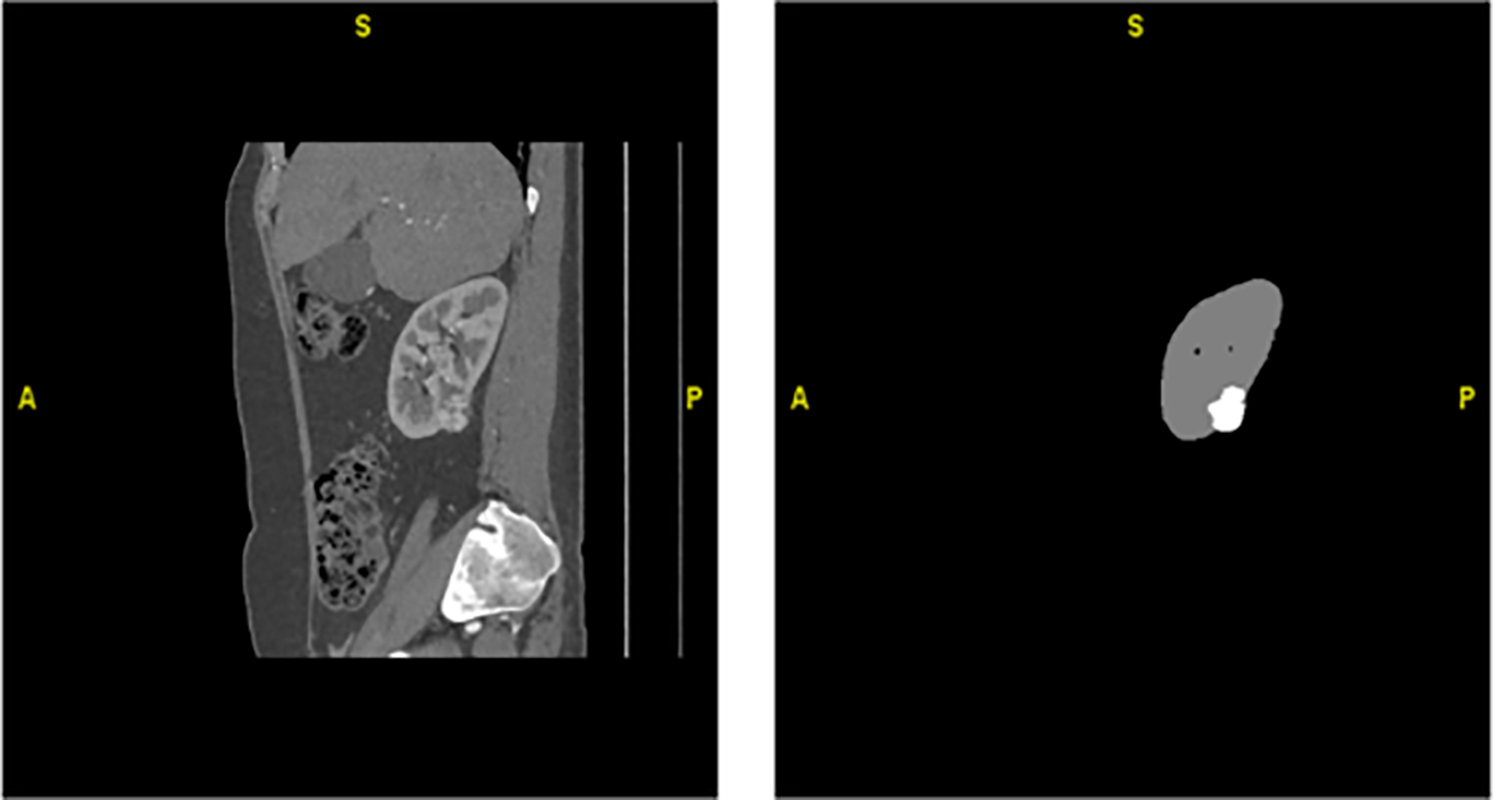

Fig. 2 represents a 2D kidney MRI slice from the TCGA-KIRC dataset, shown after intensity normalization using HU mapping. The overlaid mask illustrates tumor (red) and normal kidney (green) regions used for supervised training and evaluation. It is important to note that while 3D U-Net performance values are cited as baselines, 3D U-Net is not a component of the proposed hybrid model. Instead, it serves only as a comparative reference for volumetric kidney segmentation. Our hybrid framework uniquely integrates CU-Net, Mask R-CNN, SFMNN, and IMBKM+EDCNN specifically for kidney tumor segmentation on TCGA-KIRC. The proposed CU-Net was implemented with four encoder–decoder stages, utilizing dilated convolutions, residual skips, and dropout (0.3), whereas Mask R-CNN employed a ResNet-50 + FPN backbone with optimized anchor scales and ROI Align. SFMNN consisted of 3 convolutional layers with stochastic feature noise, and IMBKM+EDCNN used k = 2 clustering with a 5-layer 3D encoder–decoder. Dice + Cross-Entropy loss was applied for CU-Net, standard Mask R-CNN losses for instance masks, and Dice loss for final fusion. Models were trained with Adam (lr = 1e−4, batch sizes 2–8 depending on the model, 100 epochs, and early stopping), using augmentations (rotations, flips, elastic deformations, contrast/brightness shifts, and Gaussian noise). Fusion weights (α = 0.6, β = 0.7, γ = 0.5) were optimized via grid search.

Figure 2: Hounsfield Unit (HU)–transformed MRI slice and corresponding ground-truth mask